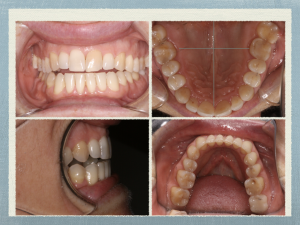

clinical dental photos

Impaired Mouth clues

clincial dental photos